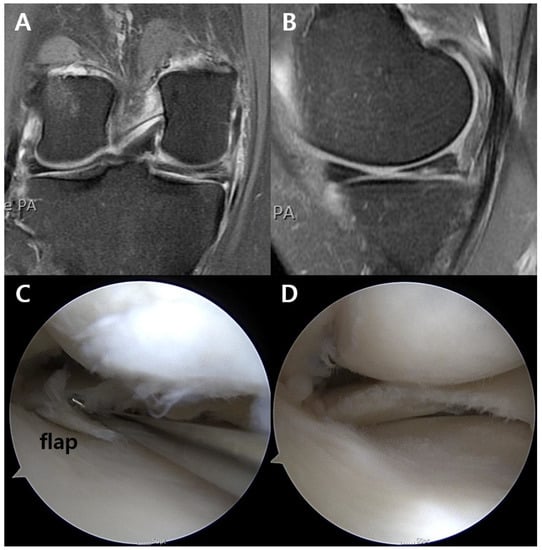

Figure 2.

Receiver operating characteristic curve for unstable flap showed that the cutoff point of symptom duration was 14.0 months, with the area under curve being 0.70 (sensitivity, 50.0%; specificity, 83.7%).

Based on univariate analyses, age, symptom duration, cartilage wear of the femoral condyle and the tibial plateau, and subchondral BML were included in a multivariate logistic regression analysis. The results showed that symptom duration (p = 0.026, odds ratio = 0.99) and high-grade cartilage wear of the medial femoral condyle (p = 0.017, odds ratio = 0.06) were negatively associated with an unstable flap (Table 2). An ROC curve was used to calculate the symptom duration at which the sensitivity and the specificity for unstable flaps were maximized (Figure 2), and the cutoff point was 14.0 months, with the area under curve being 0.70 (sensitivity, 50.0%; specificity, 83.7%).